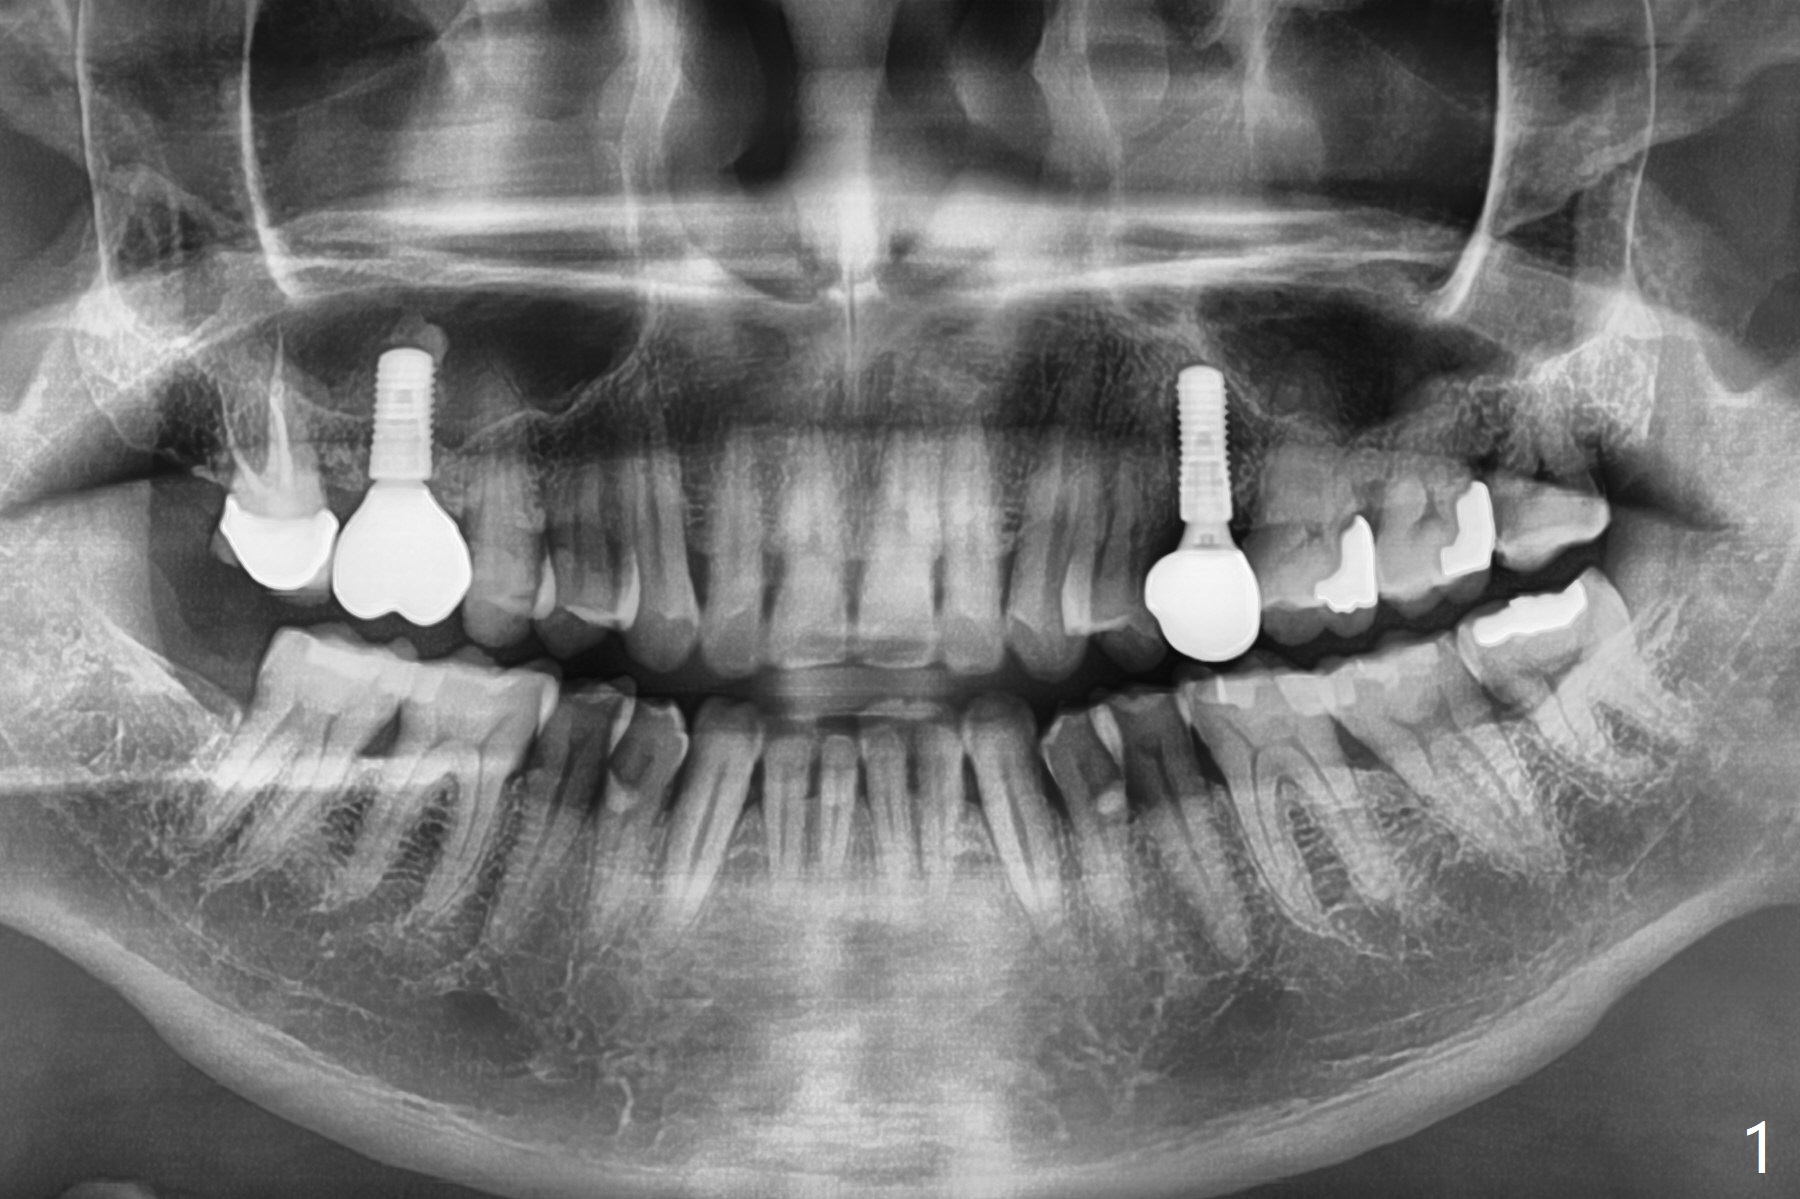

61岁男在拔除左上智齿后5个月拔除左下智齿(图一,最有可能使用Osteogen Plug),术后愈合正常(图二)。